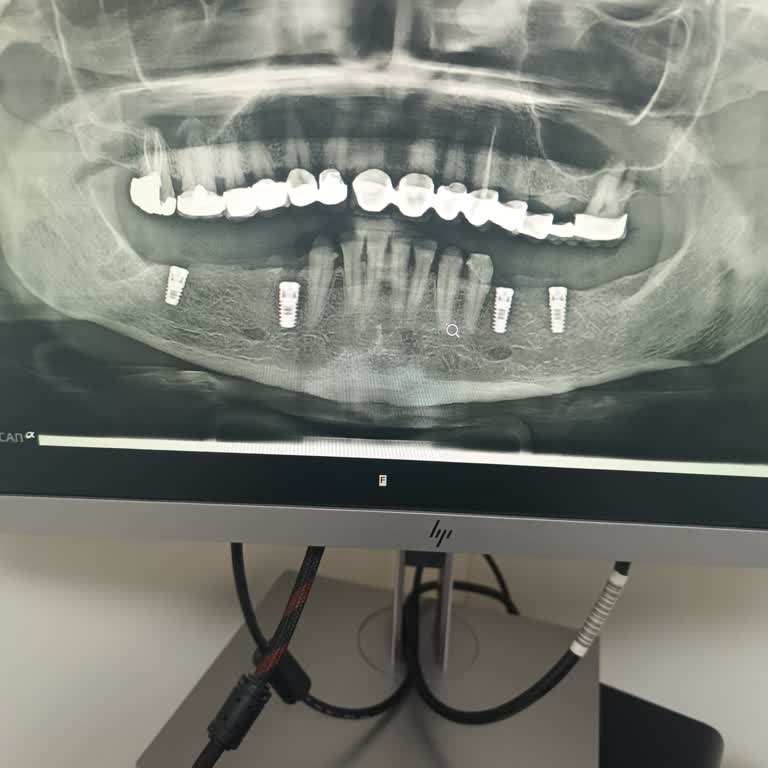

2022 Ocak ayında İstanbul Bağcılar Erkut Ağız ve Diş Sağlığı Merkezi’nde E***** E*** tarafından gerçekleştirilen implant işlemi sırasında, işlem öncesi ve sonrası röntgen çekilmeden uygulama yapıldı. Bu nedenle implant yanlış yerleştirildi ve sinir hasarı oluştu. İşlem için IBAN üzerinden 4.000 TL ö...